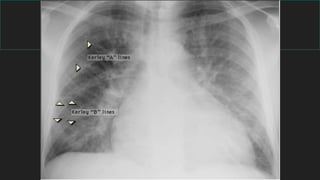

Signos radiológicos principales

Enfermedad pulmonar

difusa

LINEAL

Líneas de Kerley

Edema intersticial

ICC

INSUFICIENCIA CARDIACA

Recuerde los 4 signos radiológicos:

 1) Lineas B Kerley

 2) Congestión peribronquial

 3) Liquido en las cisuras

 4) Derrame pleural

 CARDIOMEGALIA